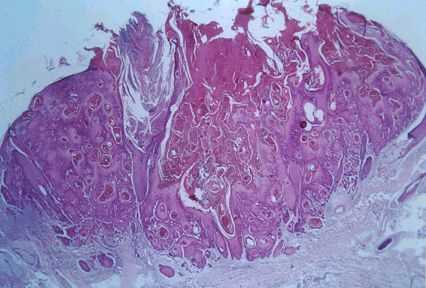

The above specimen is taken from a middle-aged man. What are the features? Answer A raised lesion with acanthosis and central core of keratin. The base of the lesion is well-demarcated without evidence of deep invasion. Is excision necessary for this condition? a Answer While this lesion may resolve spontaneously, it can leave an unsightly scar. Excision is the treatment of choice. In addition, keratoacanthoma may sometimes be indistinguishable from squamous cell carcinoma and total excision (including the base) allow a more thorough histological examination.